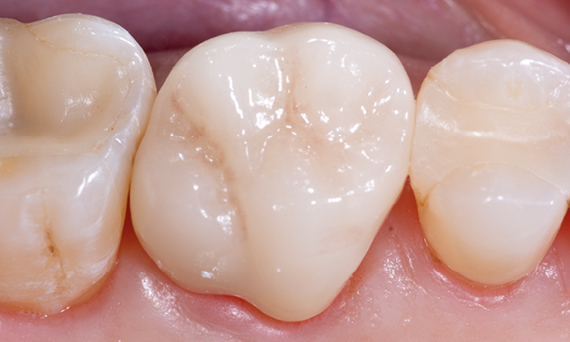

Before: First upper molar had been restored with an extensive yet insufficient composite filling that already showed visible fractures.

After: Chairside-fabricated restoration made from an advanced lithium disilicate ceramic, CEREC Tessera.